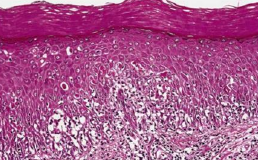

Pemphigus

天疱瘡

自體免疫疾病

vulgaris (PV,常見) Ab 打 Desmosomes 50y

• 不結疤,眼球不沾黏

• 口腔病變 first come, last go

• Desmoglein 3: 口內

• Desmoglein 1: 皮膚表層

• 大水泡,薄水泡,破水泡

• Nikolsky sign

• row of tombstones: 只剩 Basal cell 像 Cleft 突出去

• acantholysis → Tzanck cell (飄落在Celft 中)

• 上皮細胞之間沉積抗體(IgG, IgM)和補體(C3)

• 濃度與臨床症狀嚴重度相關